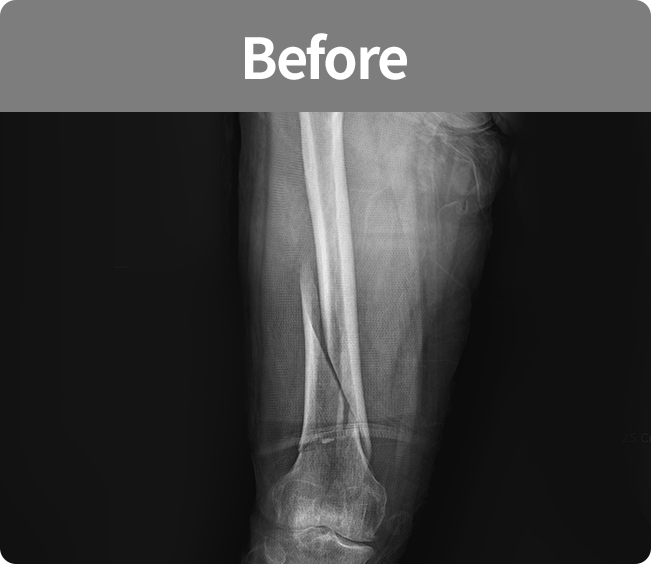

골절 고정술

부러진 뼈를 해부학적 위치로 정확하게 맞춘 뒤,

뼈가 안정적으로 붙을 수 있도록

금속판, 나사, 핀 등을 이용해

고정하는 수술(내고정술, 외고정술)

뼈가 안정적으로 붙을 수 있도록 금속판, 나사, 핀 등을 이용해 고정하는 수술

(내고정술, 외고정술)